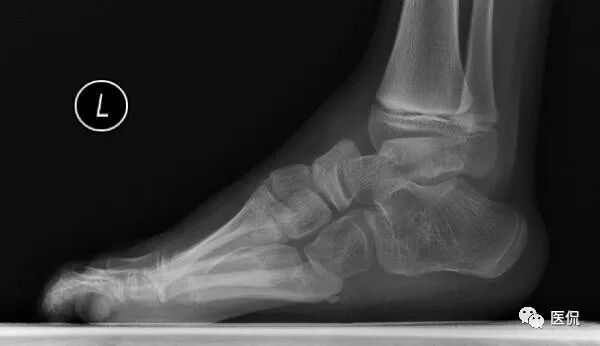

本病例临床病史示双足内翻、内收,呈马蹄状,X线整体观及个骨形态的改变与之相对应。负重X线侧位片显示足内弓减小,足外弓增大,舟骨发育不良,距舟关节半脱位,跟距角明显减小。

足部负重侧位片:跟骨马蹄位,其上下径增大;舟骨外侧发育较小,距舟关节半脱位;即使强迫前足向背弯曲,其较后足仍向足底弯曲(弓形足);跟距角变小(正常25-45度),严重时跟骨与距骨中轴线近似平行。

先天性马蹄内翻足

先天性马蹄内翻足是足部常见的先天性畸形,发病率约为0.05-0.2%,发病率在各种族间存在一定差异,在中国约0.051%。为男性发病较多,可为单侧发病,也可双侧,80%为先天性。关于先天性马蹄内翻足病因、病理及发病机制国内外尚无统一说法,目前倾向于多基因参与且受环境因素影响胚胎期异常发育的结果。遗传因素显然发挥了重要作用,显示双胞胎其中一个有先天性马蹄内翻足,另一个出现先天性马蹄内翻足的机率为33%,在所病例中约25%的是家族性。PITX1基因,其编码几乎完全在下肢中表达的转录因子,是涉及马蹄足的第一个基因。与胚胎肢体发育相关的基因有:Hox、Tbx、Pax、Myod等,目前已有HoxD、Pax与先天性马蹄内翻足相关性的研究。

先天性马蹄内翻足由足下垂、内翻、内收三个主要畸形综合而成。以后足内翻、内旋,前足内收、内翻、高弓,踝关节马蹄为主要表现的畸形疾病。关于先天性马蹄内翻足的评估,包括足部形态学评估、足部功能评估及影像学评估等。其中影像学评估主要是通过客观测量马蹄足跗骨间关系的各种角度来进行的,对临床治疗及治疗后的疗效评价有着非常重要的意义。婴儿马蹄内翻足的跗骨形态大多不规则,难于划出其轴线,其骨核常常是偏心的,并且其骨化中心发育落后于正常足。3D-CT图像能直观显示足部各骨的形态及其空间关系,3DCT的旋转和切割技术,可在最佳位置和角度来评定马蹄足的内翻程度和观察各骨之间的空间关系,可作为马蹄内翻足的X线片的有效补充手段。MRI可显示软骨的形态,为本病的评估提供新的检查方法,尤其适用于婴幼儿马蹄足的分类。有学者认为能更好的显示婴幼儿马蹄足跗骨的各种病理变化,更能直观准确的描述各跗骨的位置及其相互关系。超声检查评价先天性马蹄内翻足具有很大的临床意义,由于超声检查非常容易进行,费用便宜,非骨化结构可被直观看到,还可以避免X线辐射。